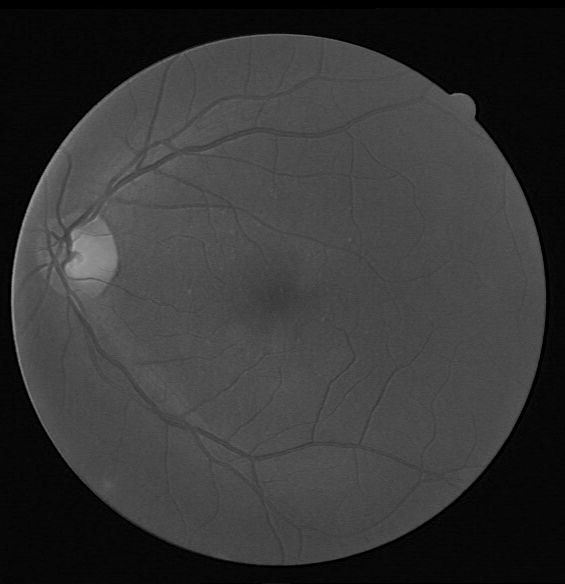

Refer to caption

(a) Original image in RGB

(b) Red channel

(c) Green channel

(d) Blue channel

Figure 2: Sample DRIVE image and its channels.

The proposed BLCB-CNN methodology comprises a few components that address the challenges posed by typical retinal fundus images. Figure 1 shows the sequential workflow of these components. The proposed BLCB-CNN methodology extracts the green channel of the input retinal fundus image, which has maximum contrast among the three channels of the RGB fundus image [36]. Figure 2 depicts an original sample DRIVE image with all its separated channels, i.e., red, green, and blue. Additionally, pre-processing of the input retinal fundus image is performed using GCN [43], CLAHE, and gamma corrections to increase intensity uniformity as well as to enhance the contrast between vessels and background pixels. Figure 3 depicts the extracted green channel of a sample DRIVE image, and other images are illustrations of pre-processing steps performed on the green channel. After pre-processing, the images are input sequentially to the two major components of the proposed BLCB-CNN methodology architecture, i.e., Patch Extraction (Section II-A) and Class Imbalance Handler (Section II.B).